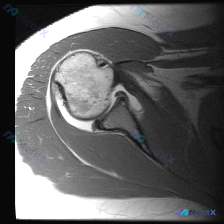

看到一个肩关节MRI矢状斜位T2序列的病例,临床关注盂唇病变,但影像分析提示: - 关节盂唇形态尚可,信号无明显异常增高,未见明确的撕裂、剥离等典型盂唇病变直接征象 - 冈上肌肌腱附着处完整,未见全层中断或高信号裂隙 - 肩峰下间隙结构尚可,无明显撞击征象 这类影像阴性但临床有肩痛的病例,大家的鉴别...